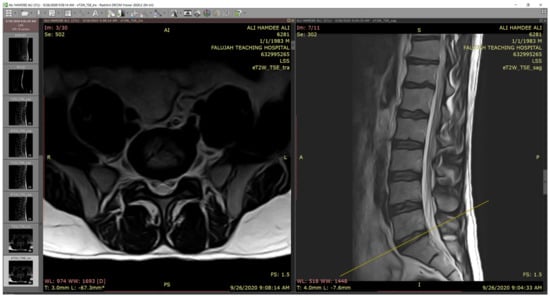

The classification was conducted by using the Fatima Label (FaLa) program. We created the FaLa program to help radiologists perform the labeling process with the help of RadiAnt [40] PACS DICOM viewer. Finally, the patient’s images are displayed on computers (see Figure 2).

As we note in Figure 2, there are several lumbar spine MRI series for each patient, such as survey, Mylo, sagittal T1, sagittal T2, axial T1, axial T2, and so forth. For each series, there are many images, for example, in Axial T2, we have 30 images. So, we are likely to receive 115 DICOMs per patient. In the diagnostic process, radiologists are interested in three series: myelography, axial T2, and sagittal T2.